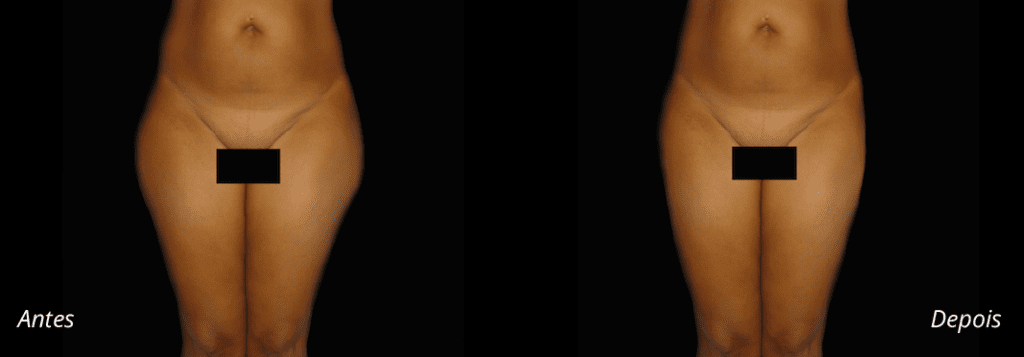

Imagens antes e depois